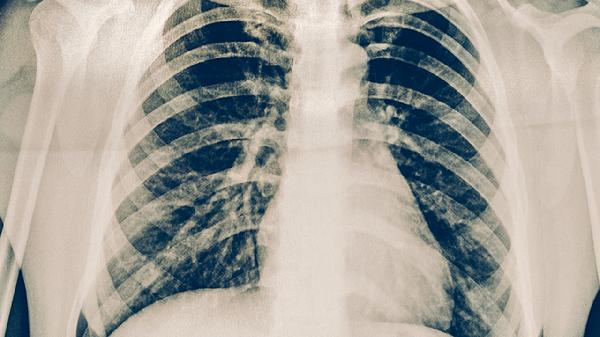

肺结节晚期症状表现

肺结节晚期症状主要表现为咳嗽加重、痰中带血、胸痛、呼吸困难和体重下降。肺结节可能是肺结核、肺炎、肺脓肿、肺癌等疾病引起的,建议患者及时就医。